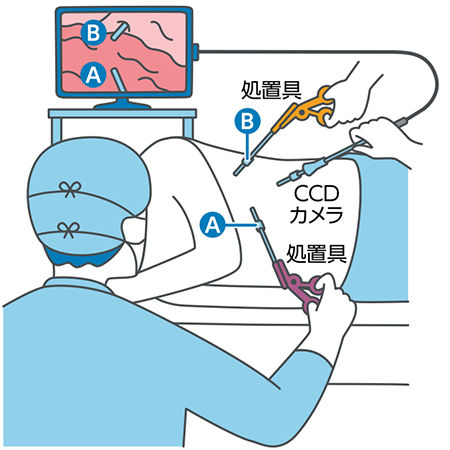

胸腔鏡(内視鏡)手術とは?

肺がん手術には、古くから行われている外科手術的な開胸術と、胸腔鏡という内視鏡を使用する胸腔鏡手術があります。

開胸術は、肩甲骨の下から胸にかけて15〜20cmほど切開し、肋骨を広げて肺を切除します。

一方、胸腔鏡手術は、胸を数ヵ所小さく切開し、そこから小型電子カメラがついた胸腔鏡や鉗子、自動吻合機などの手術器具を挿入して肺を切除します。胸腔鏡手術には、モニターだけを見ながら手術する完全胸腔鏡下手術(VATS;バッツ)と、胸腔鏡を挿入してモニターを見つつ、直接目でも確認しながら肺切除を行う胸腔鏡補助下手術(Hybrid VATS;ハイブリッドバッツ)があります。

胸腔鏡手術は、切開する傷が小さいので開胸術に比べて美容的に優れているというメリットがあります。一方、デメリットは、手術中に出血が起きたときに処置が遅れる可能性があることです。手術時の出血量や術後合併症にかかる頻度、入院期間、術後の痛みなどについて従来の一般的な開胸手術と比べたところ、手術時間と出血量については胸腔鏡を用いた手術の方が優れており、再発率や5年生存率についても同等であるという報告もあることから、Ⅰ期(ステージ1)の非小細胞肺がんの手術方法として推奨されています。